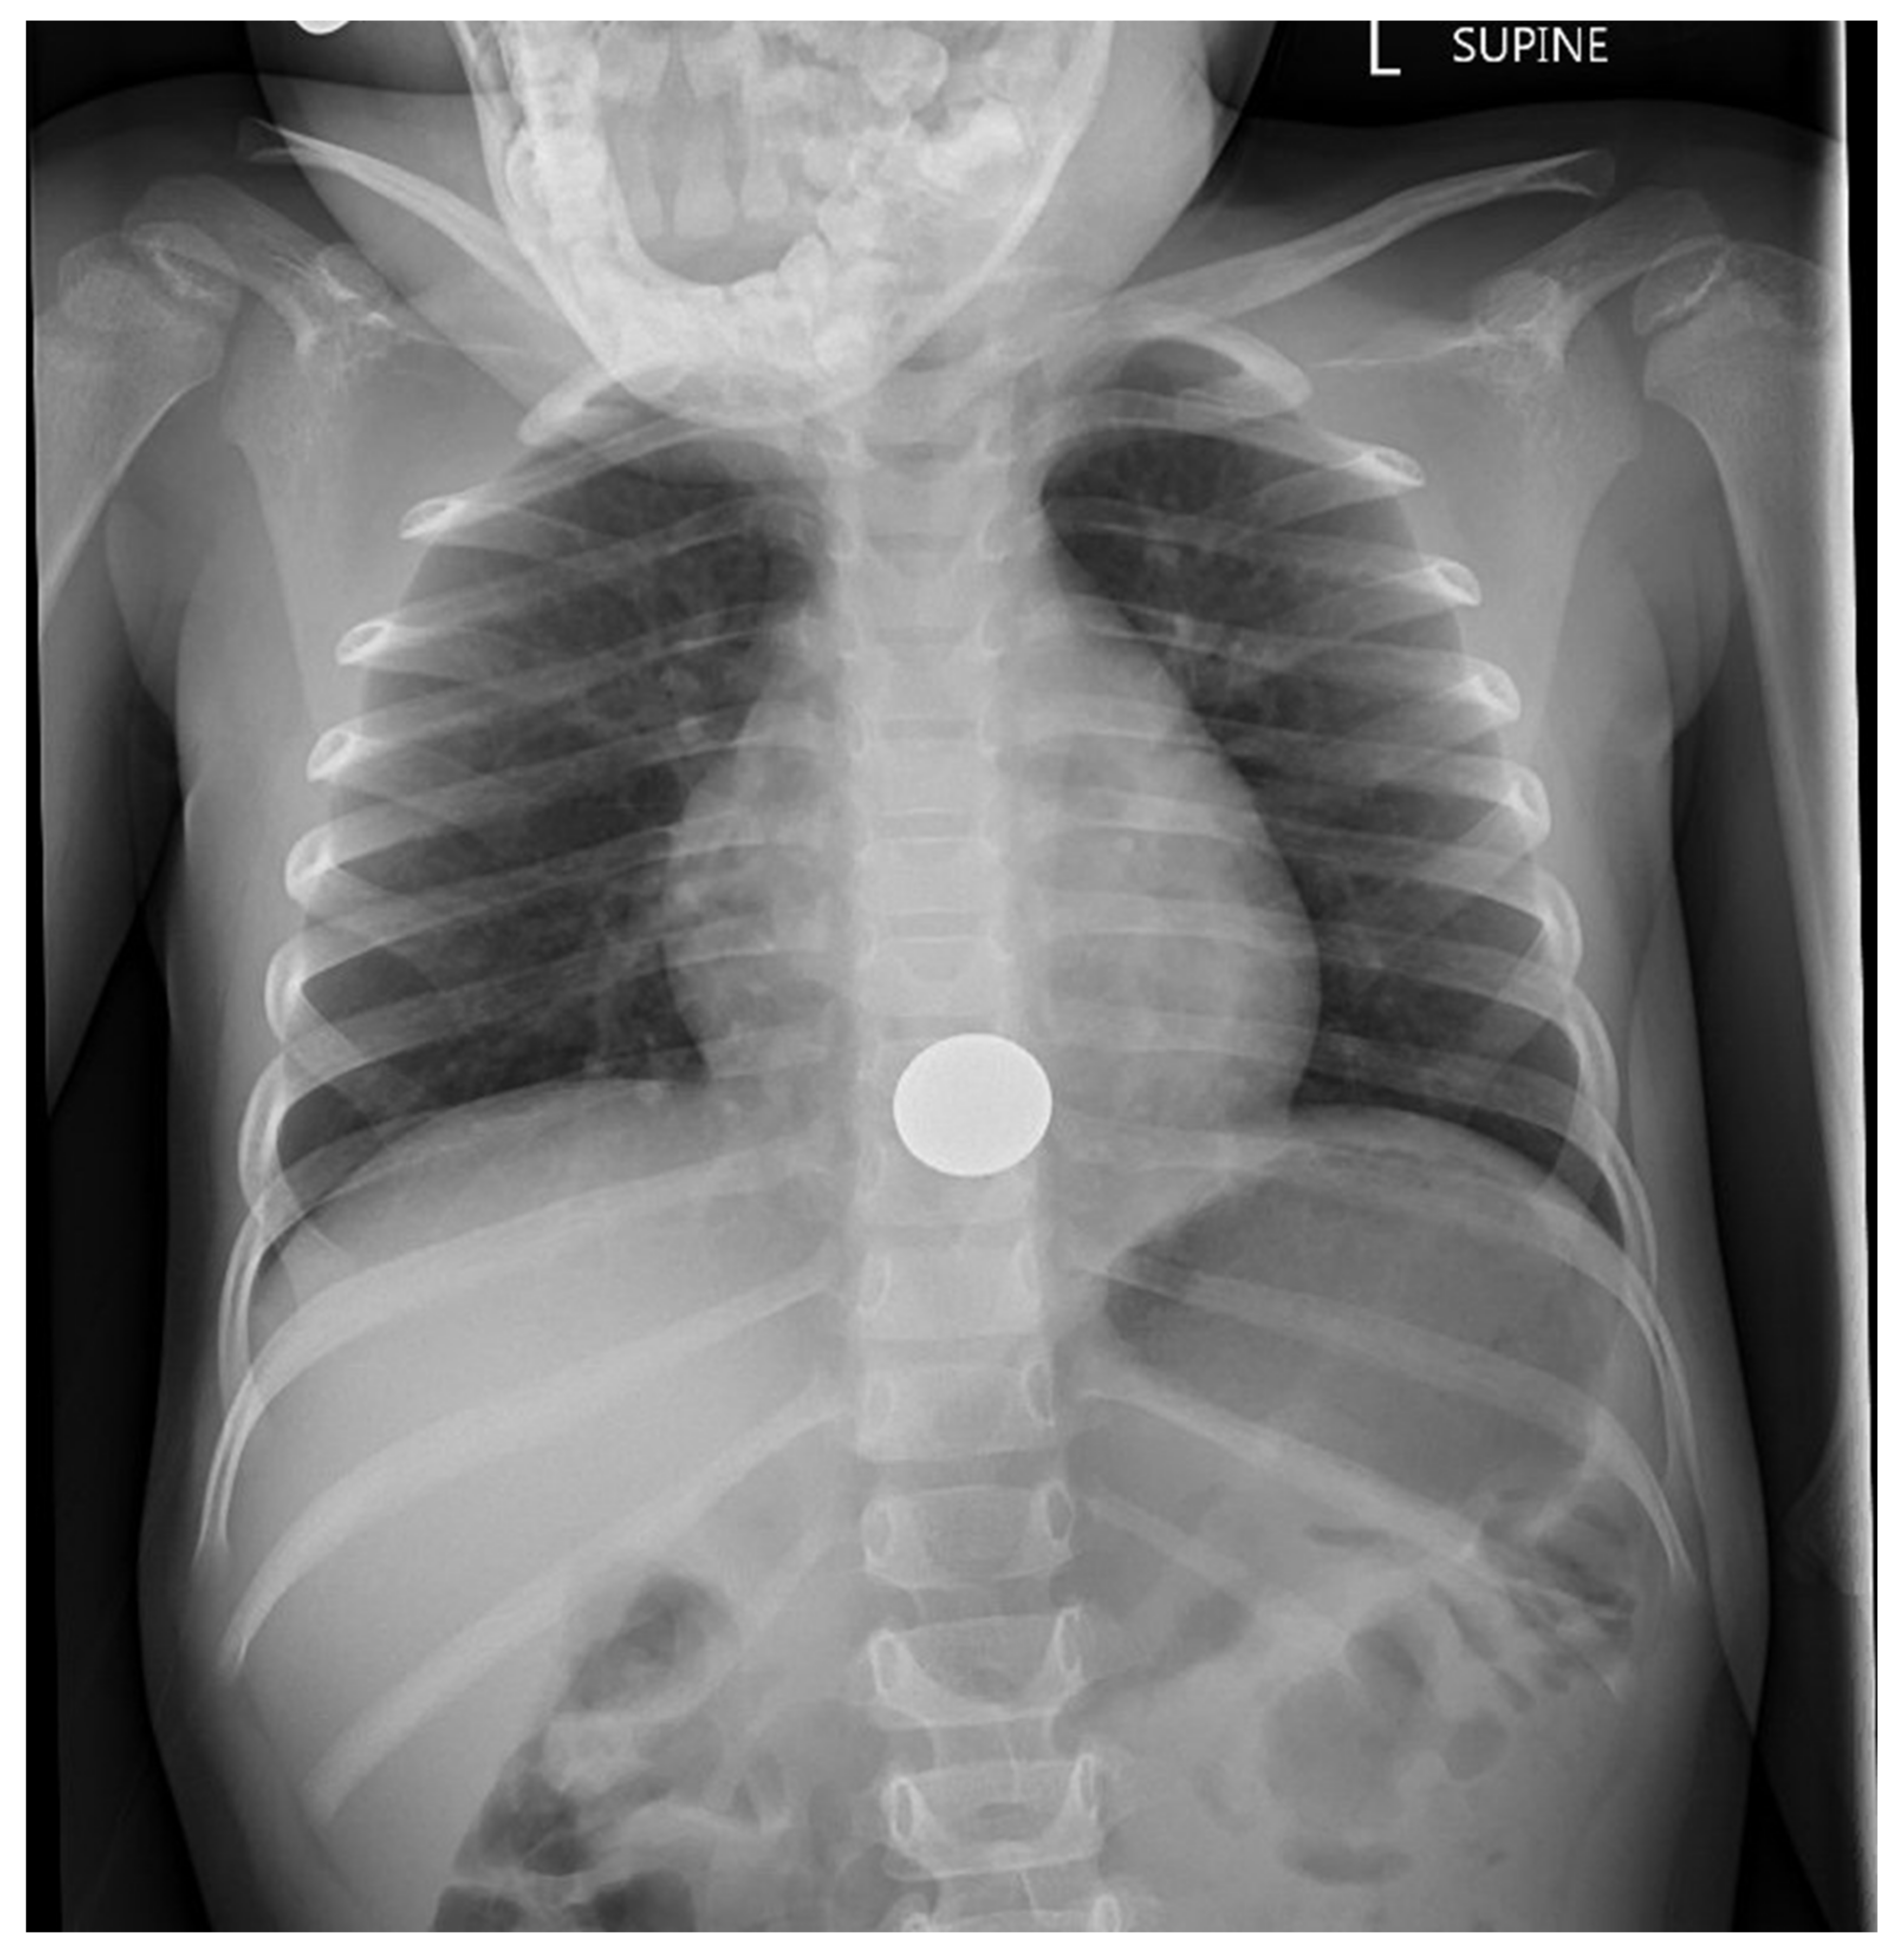

Coins are, by far, the swallowed foreign bodies most commonly brought to medical attention [8]. Thus, there has been substantial literature on coin ingestion. In the United States, children swallow far more pennies than other coins [21]. While the majority pass through the GI tract without complication, it is not uncommon for a previously healthy child to have a swallowed coin lodge in the esophagus. About 70% of coins (and similarly-shaped objects) lodge at the upper esophagus, corresponding to the area between the clavicles on frontal radiographs (Figure 1) [21]. The remainder are found lodged with about equal frequency in the mid-esophagus (Figure 2) or at the lower esophageal sphincter (Figure 3). While one-third to one-half of coins in the mid-esophagus or at the lower esophageal sphincter will pass into the stomach spontaneously in minutes to hours, especially in conjunction with oral intake, it is less common for upper esophageal coins to progress spontaneously [21]. Coins that lodge in the esophagus may partially or completely obstruct the esophagus, causing inability to swallow, or cause complications due to local pressure necrosis on the esophageal mucosa. While coins may remain in the esophagus for long periods, even years, with minimal symptoms, some migrate into the mediastinum or structures of the chest, including the aorta, with important morbidity, such as mediastinitis or creation of an aorto-esophageal fistula [8]. Occasionally, a radiograph performed in evaluation of cough, fever, dysphagia, failure to thrive, or other complaint will reveal an unexpected esophageal coin. It is often difficult to determine how long the coins have been in place. These coins may be associated with esophageal scarring, and/or have migrated into other chest structures [8]. Management will require subspecialty consultation, and likely endoscopic or surgical removal.

Figure 2.

Chest radiograph showing swallowed hardware (washer) lodged in the mid-esophagus.

Since removal of an esophageal button battery is an emergency, while children with esophageal coins may typically be managed less urgently, distinguishing between the two on radiographs is important [14]. Belief that a disc-shaped esophageal object is a coin, when it was actually a button battery, has been associated with potentially avoidable major morbidity. On frontal radiographs, a button battery has a distinctive circle-within-a-circle appearance, while a coin is more commonly a rather uniform disc [34]. An orthogonal image of a button battery will typically show a distinctive two-tier profile (Figure 4) [34]. In some instances, a magnified, digital image will reveal the distinctive appearance of a particular coin (Figure 1) [35,36]. On rare occasions, two (or more) adherent coins of different sizes may mimic the radiographic image of a button battery; when in doubt, prompt removal of any foreign body that may be a button battery is prudent [37,38].